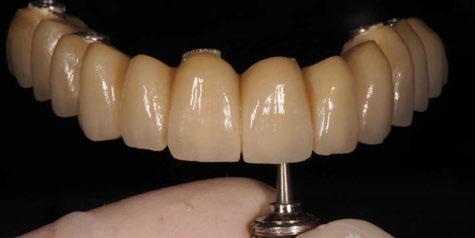

Figura 24. Provisional finalizado tras acabado y pulido en el laboratorio.

Figura 25. Provisional finalizado tras acabado y pulido en el laboratorio.

Figura 26. Entrega del provisional de carga inmediata a las 24 horas.

Figura 27. Ortopantomografía del provisional atornillado en boca para verificar ajuste.

ortopantomografía de verificación del ajuste pasivo de todos los implantes. Por último, tapamos las chimeneas con teflón y resina provisional y se chequeó nuevamente la oclusión, dando nuevamente las instrucciones de higiene y mantenimiento de la prótesis provisional (Figuras 24-27).